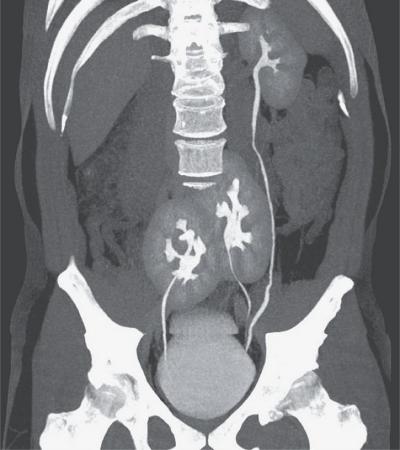

मात्र, डॉक्टरांनी जेव्हा त्याचा सीटी स्कॅन काढला तेव्हा त्यांना जे दिसलं ते पाहून तेही थक्क झाले.

इंडिया टाइम्सने दिलेल्या वृत्तानुसार, ही 38 वर्षीय व्यक्ती कंबदुखीच्या समस्या घेऊन डॉक्टरकडे गेली. काही दिवसांपासून त्याचा त्रास वाढला होता. त्याने सीटी स्कॅन केलं. (सांकेतिक छायाचित्र)

स्लिप डिस्कची तर समस्या नाही हे जाणून घेण्यासाठी त्याने सीटी स्कॅन केलं. यात स्लिप डिस्क तर नाही पण चक्क व्यक्तीला तीन किडनी असल्याचं दिसून आलं. हा प्रकार पाहून डॉक्टरही हैराण झाले.

सीटी स्कॅनने डॉक्टरांना चक्रावून सोडलं होतं. कारण त्यांनी अशी केस कधी पाहिली नव्हती. त्यांना दिसलं की, व्यक्तीच्या उजव्या बाजूला दोन किडनी आहेत. तर डाव्या बाजूला एक किडनी. म्हणजे या व्यक्तीला एकूण तीन किडनी आहेत.